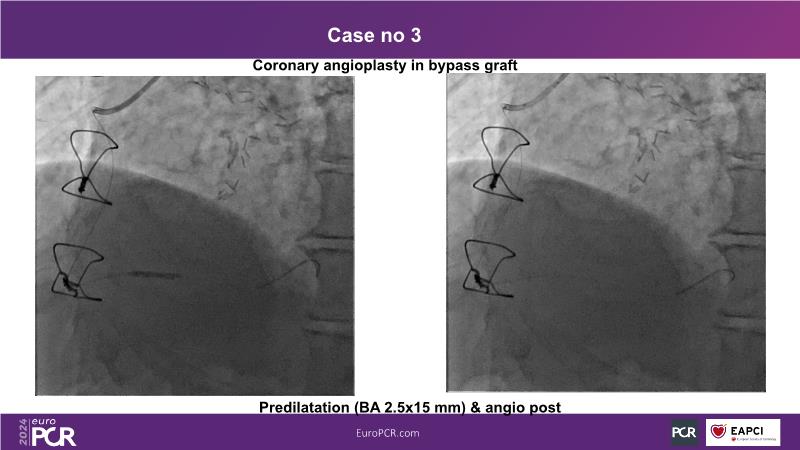

In this session, discover the effectiveness and safety of robotic PCI for both simple and complex lesions requiring additional devices like IVL, IVUS, laser, and FFR. Learn about the numerous benefits of robotics for patients and cathlab teams, including enhanced precision in wire navigation and stent positioning, full radioprotection, and reduced orthopedic injuries. Explore the growing interest in robotics within the interventional cardiology community, anticipate future technical advancements, and understand how AI will accelerate the integration of robotics and vice versa.

- To learn about a robotic PCI step-by-step from real-life experience